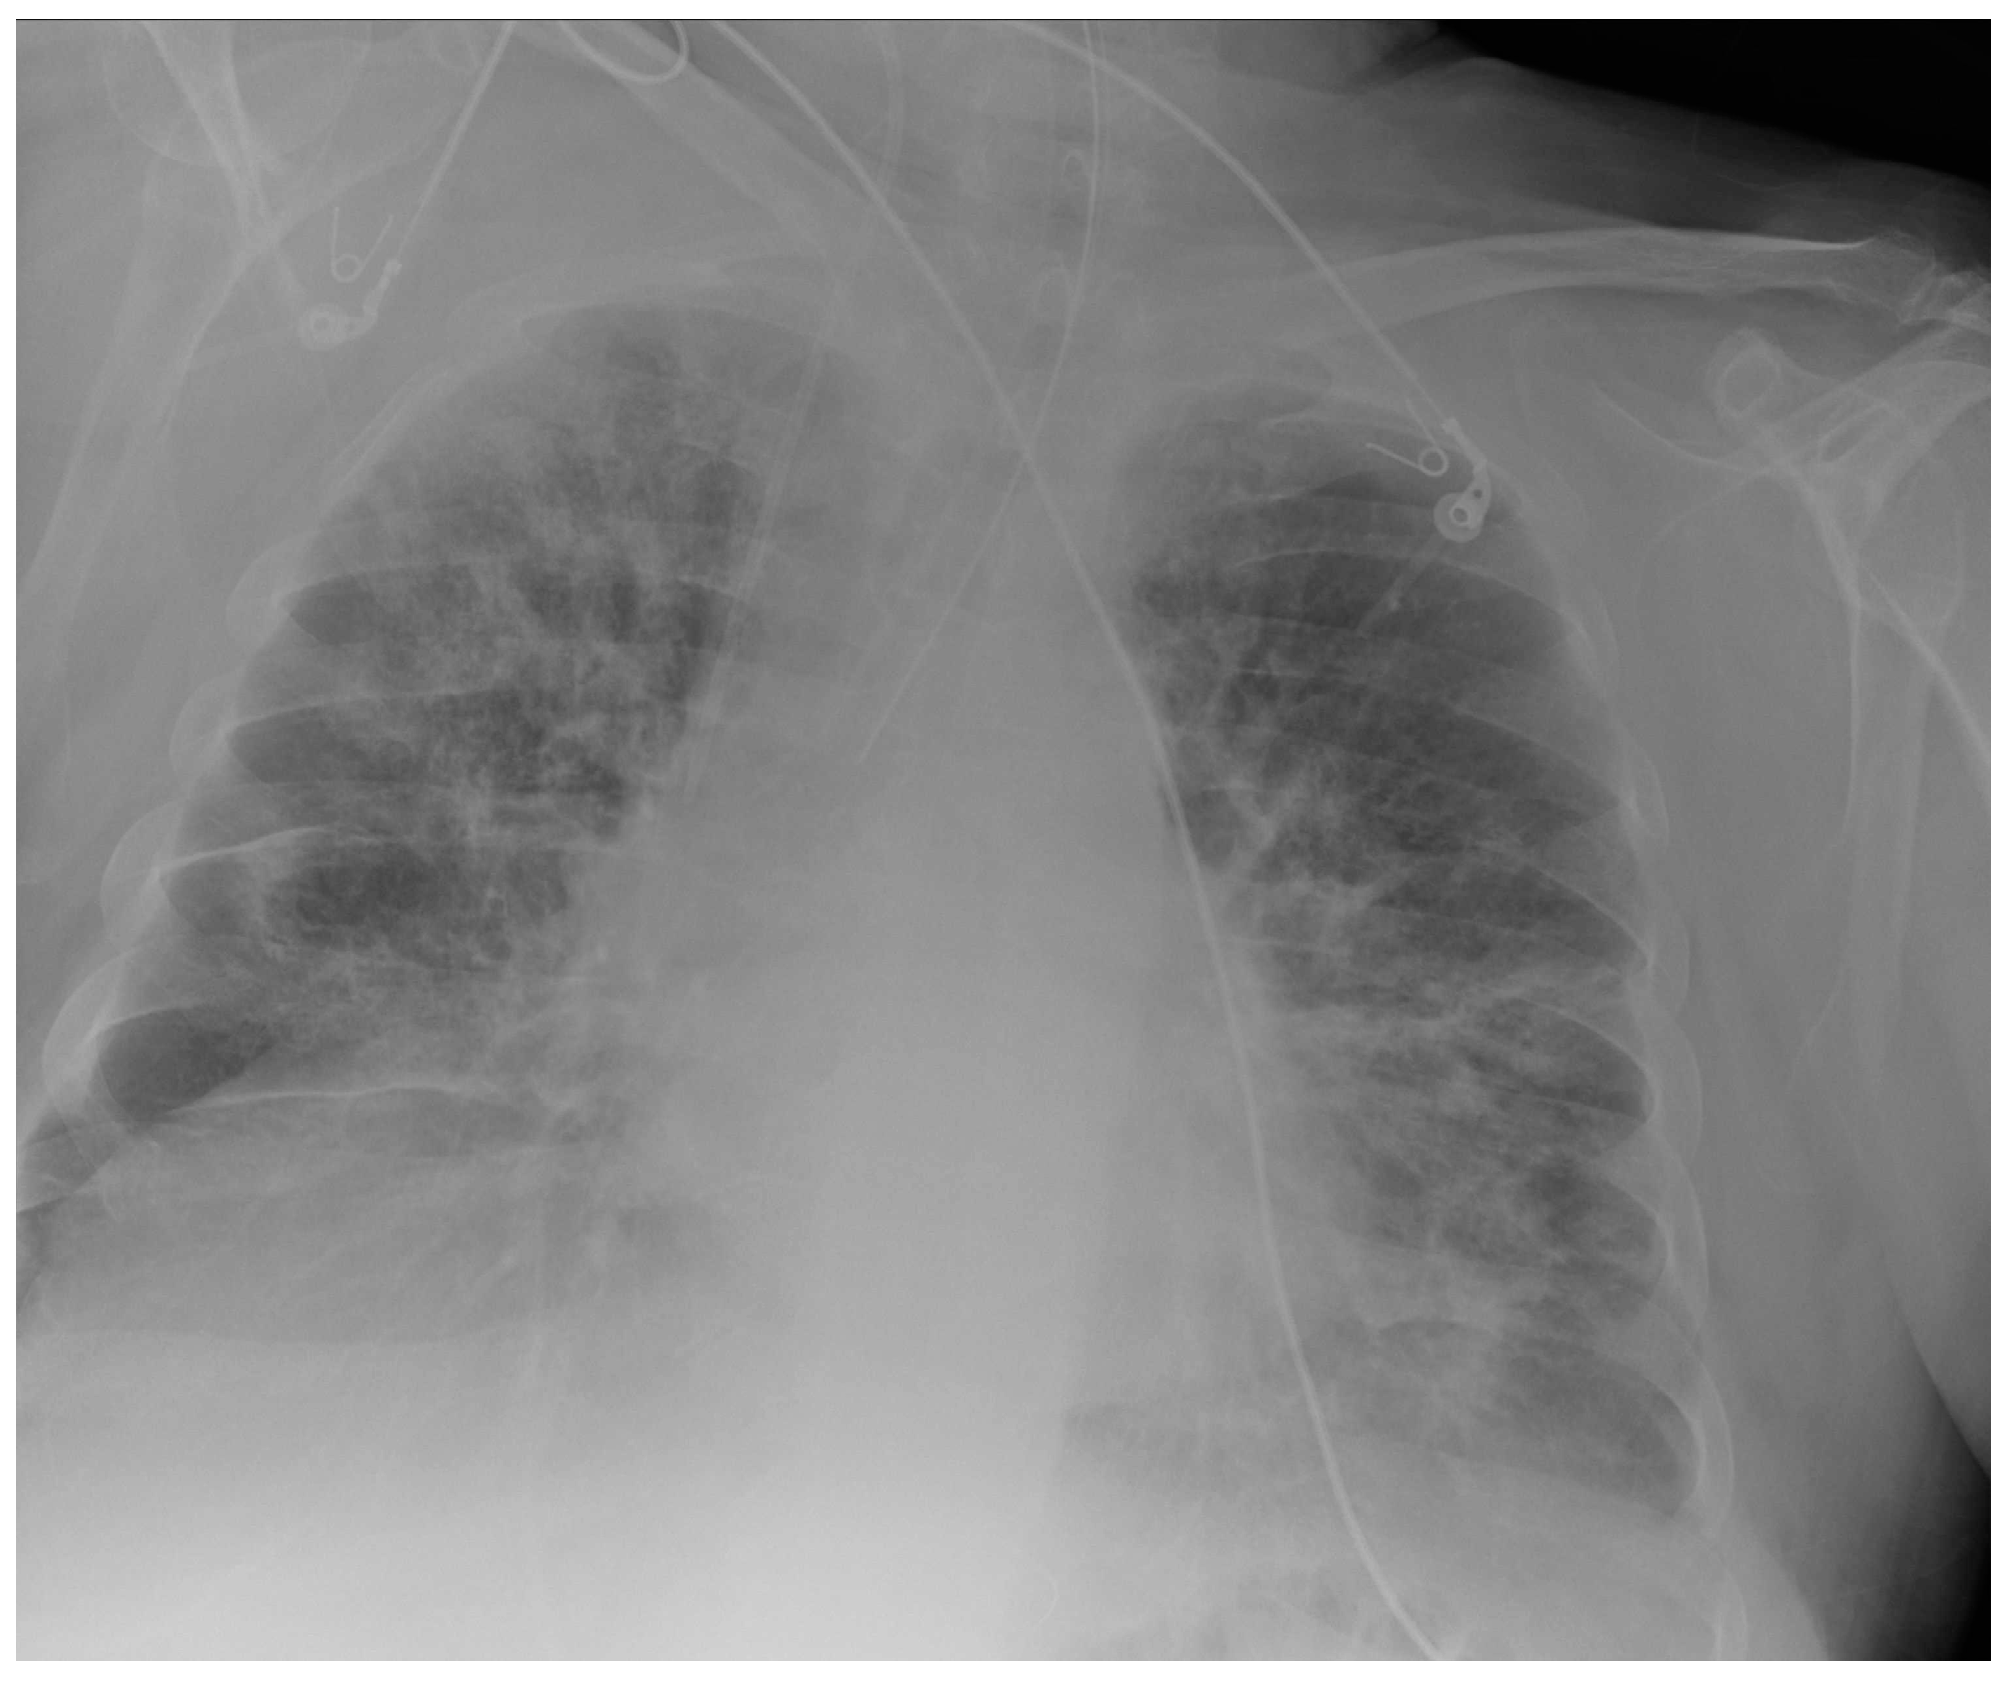

3.1. Central Vein Catheter (CVC)